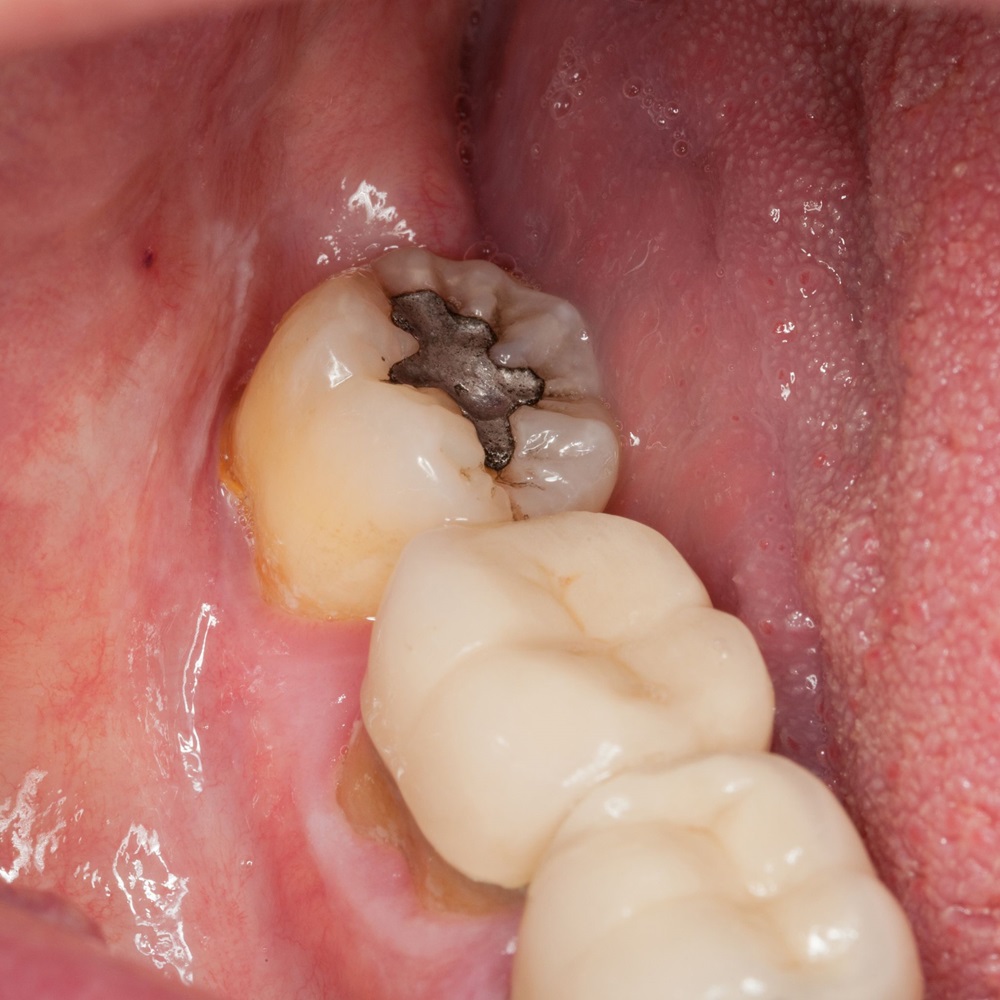

Trám răng

Đây là phương pháp được áp dụng cho những trường hợp răng khôn bị sâu nhẹ, mọc thẳng và không ảnh hưởng đến các răng lân cận. Quy trình trám răng được thực hiện bằng cách:

• Bước 3: Dùng vật liệu trám để lấp đầy lỗ sâu và ngăn vi khuẩn phát triển. Vật liệu này sẽ có màu giống với răng thật nên bạn hoàn toàn có thể yên tâm về tính thẩm mỹ của phương pháp này.